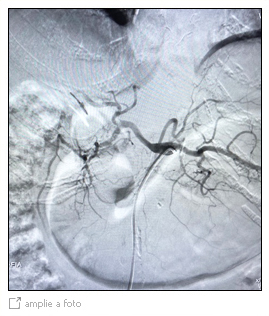

Embolização de Hemorragia Digestiva